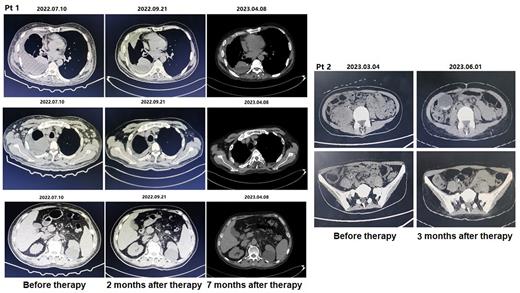

Seven patients with R/R B-NLH or even failure of anti-CD19 and CD22 chimeric antigen receptor (CAR) T cell therapy received InO combined with reduce dose R-GDP combination therapy. All patients received Rituximab (R) 375mg/m 2 intravenously (IV) on day -1, and InO 0.8 mg/m 2 (IV) on day 0. Then Gemcitabine (G) 500-1000mg/m 2(IV), Dexamethasone (D) 40 mg/day (IV) on day 1-4 and Cisplatin (P) 40-75mg/m 2 (IV) on day 1 of each 21-day cycle (±2 days). Treatment was continued for up to two cycles unless progressive disease (PD) or intolerable toxicity occurred. The primary endpoint of this study was the Complete remission (CR) and Overall response rate (ORR). The secondary endpoint of this study was Progression-free survival (PFS), Overall survival (OS) and Adverse events (AE), particularly hematological toxicity. In our study, the response evaluation was detected using computed tomography (CT) or PET-CT.

Seven patients with R/R B-NLH received 1-2 cycles of InO combined with reduce dose R-GDP therapy. Three patients did not respond to anti-CD19 and CD22 CAR-T cell therapy or their disease progressed again. The other four patients did not respond to more than 3 lines of combined immunochemotherapy and never achieved Partial response (PR) or CR. Four patients with R/R B-NLH who received 1-2cycles of InO combined with reduce dose R-GDP therapy achieved CR and survived to this day. Three of the four patients had previously received anti-CD19 and CD22 CAR-T cell therapy. Two patients with R/R B-NLH achieved PR after one cycle of InO combined with reduce dose R-GDP therapy, the other one patient achieved Stable disease (SD) only. One R/R B-NLH patient who achieved CR after one cycle of this salvage therapy had a PFS of one year to date without any other treatments. The other three R/R B-NLH patients who achieved CR after 1-2 cycles of this salvage therapy had a PFS of 3-6 months without any other treatments. The other two patients who achieved PR after 1 cycle of this salvage therapy survived 7 months and 2 months, while the only one patient who achieved SD survived one month without any other treatment. The main AE of this study was hematological toxicity. Three patients were defined as 3-4 grade of neutropenia, four patients were defined as 3-4 grade of anemia and three patients were defined as 3-4 grade of thrombocytopenia in this study. Except for one patient who was defined as grade 3 of thrombocytopenia recovered nine months after this salvage therapy, all other patients recovered two to three months after this study. There have been no deaths from severe infections due to hematological toxicity.